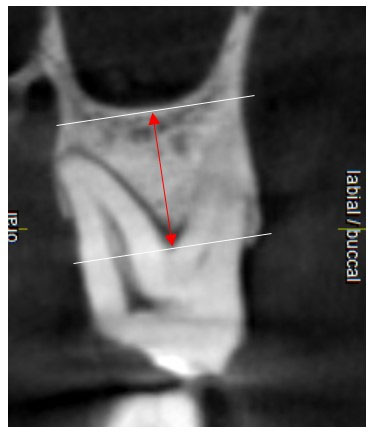

The shortest distance to SF from each root apex was recorded in the coronal slice (Figure 4).

Figure 4.

This figure shows an example of the measurement recorded for the distance of the mesiobuccal root apex to SF. In all the images, the closest point to SF was selected.